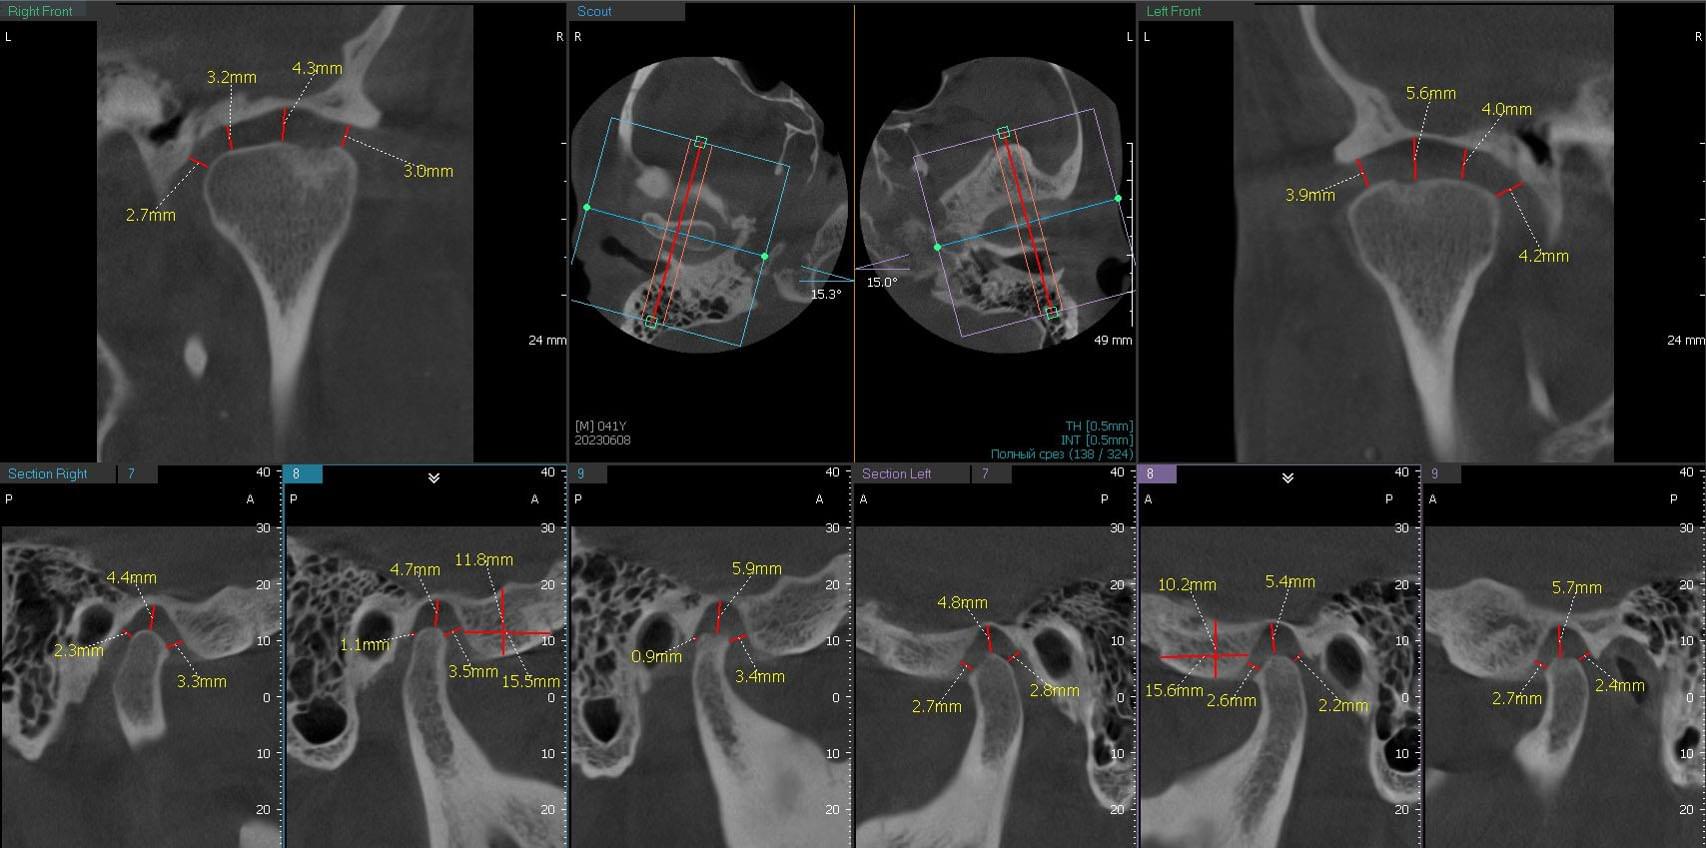

Дисфункція скронево-нижньощелепного суглобу

Якщо ви маєте сумніви щодо свого скронево-нижньощелепного суглобу, компанія MyRay Lab є вашим надійним партнером у діагностиці та визначенні причин цієї дисфункції. Ми спеціалізуємося на проведенні КТ-досліджень суглобів, черепа та навколишніх тканин, що дозволяє нам докладно оцінити структуру та функцію скронево-нижньощелепного суглобу.

Однією з головних переваг співпраці з MyRay Lab є наша високотехнологічна устаткування, що використовується в процесі КТ. Ми застосовуємо передові технології, які забезпечують зображення високої якості та дозволяють отримати детальну інформацію про стан суглобу. Наша компанія MyRay Lab використовує інноваційні методи та підходи, щоб допомогти нашим клієнтам у точному діагностуванні та розумінні проблем щодо їх скронево-нижньощелепного суглобу.

Здоров'я наших клієнтів є нашим пріоритетом, тому ми пропонуємо індивідуальний підхід до кожного пацієнта, що звертається до нас для діагностики дисфункції скронево-нижньощелепного суглобу. Наші досвідчені фахівці використовують комбінацію клінічного дослідження та КТ-сканування, щоб з'ясувати причини симптомів та розробити ефективний план лікування.